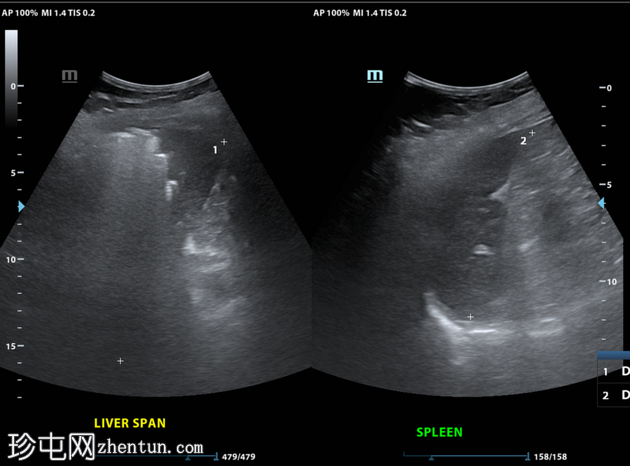

12小时后

超声

纵切面(肝脏

第6和第7段)

9.jpg

将穿刺针插入第6段肝脓肿。抽取血脓性液体。

插入导丝,扩张通道,然后插入猪尾导管。猪尾导管用引流锁固定。导管尖端位于肝脓肿内。

对肝包膜下积液重复相同操作(未显示)。